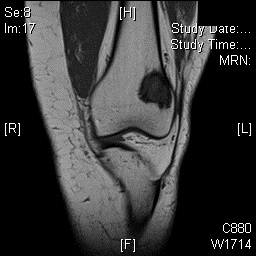

MRI

• MR Imaging, demonstrates intermediate to hypointense signal on T1-weighted images (Fig. 4 & 5) and hyperintensity on T2-weighted images (Fig. 6 & 7).

Fig. 4

Fig. 5

Fig. 4 & 5: MR Imaging. Axial (Fig. 4) and Coronal (Fig. 5) T1 weighted image demonstrates a well-defined T1 hypointense mass within the femur with a more hypointense border corresponding to the sclerosis noted on the CT